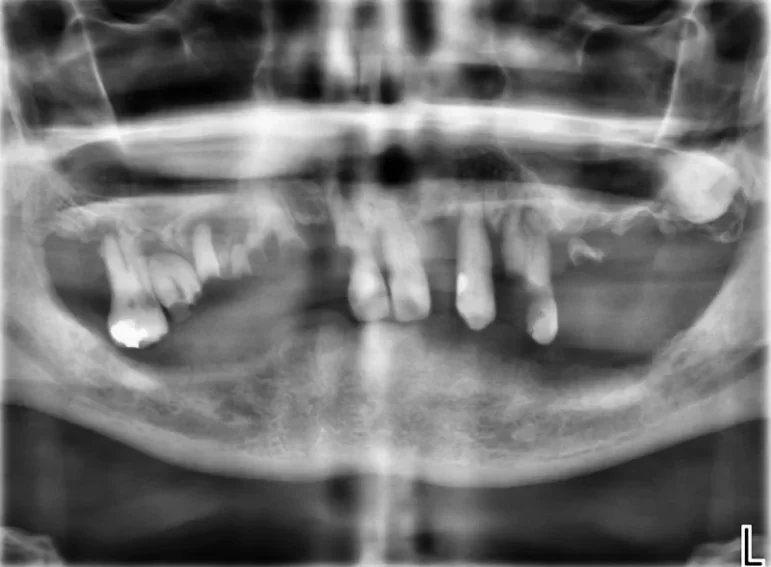

Case 37 – Implants

Upper complete denture and lower implant retained complete denture